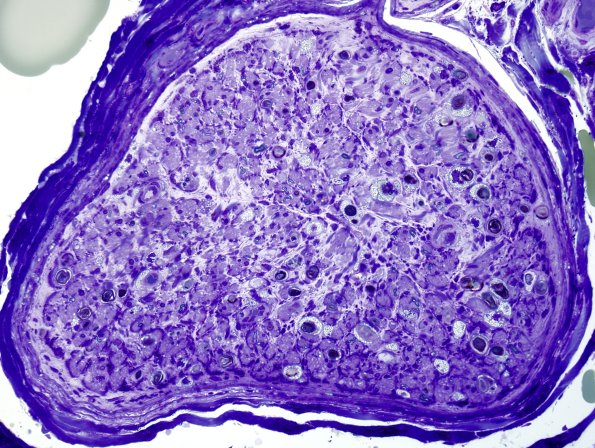

4A1-3 In this case there are numerous Schwann cells with lipid droplets and possibly some macrophages contributing as well.